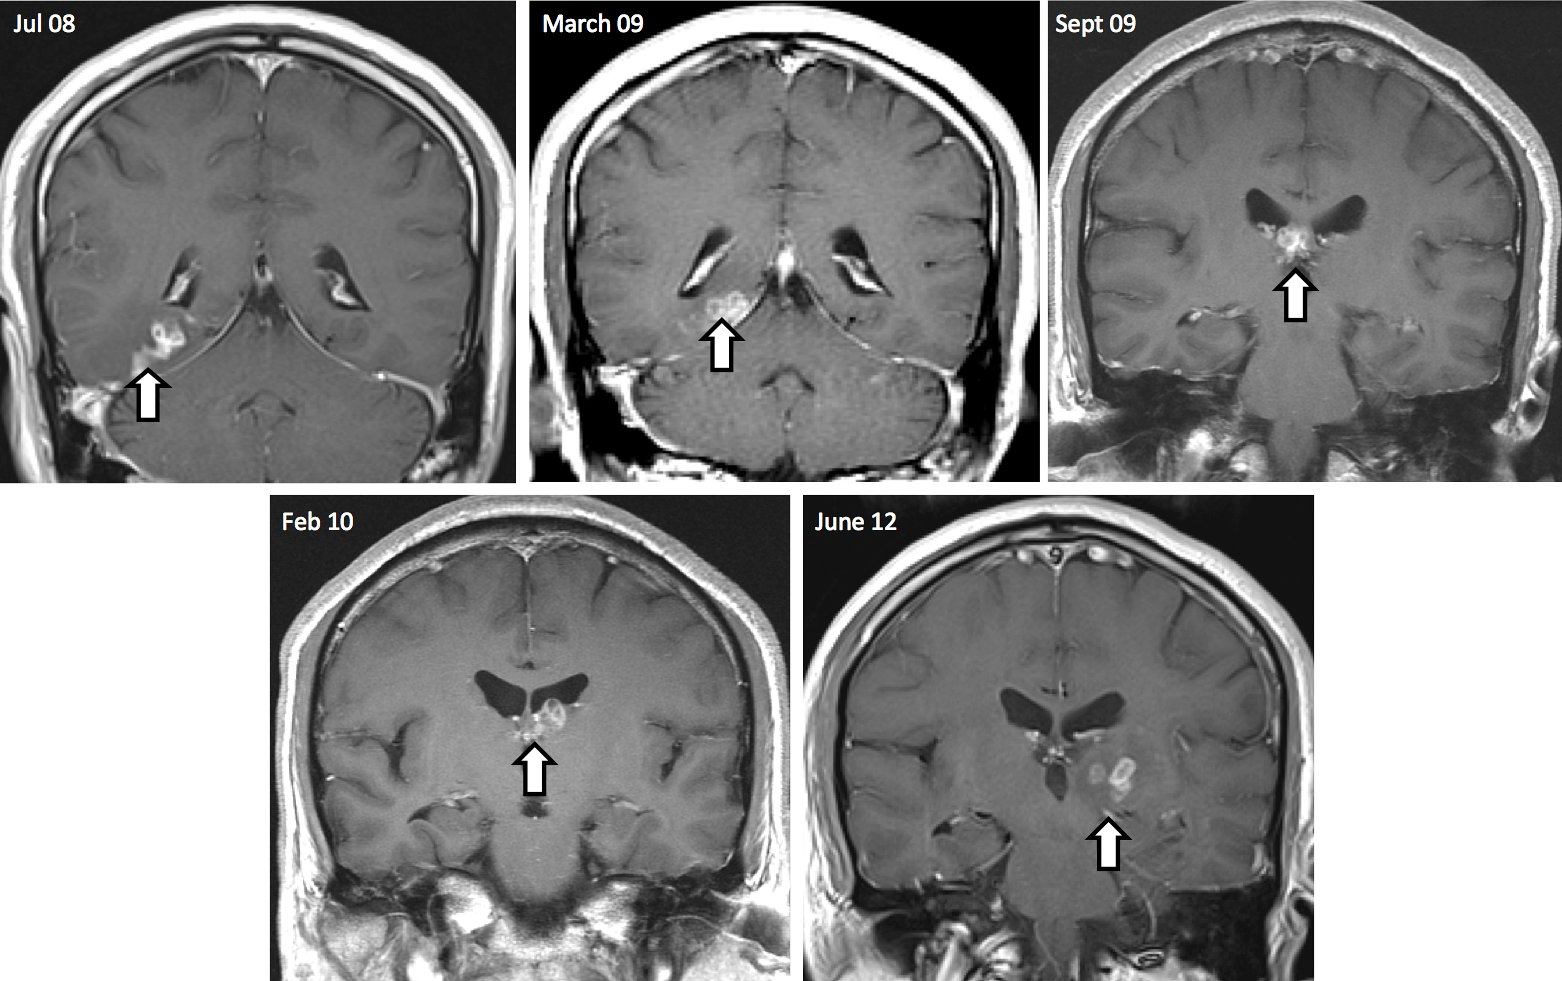

In four years, the worm traveled 5 centimeters from the right side of the brain to the left, as shown by the cluster of lesions the larvae produced. Genome Biology 2014, 15: 510

Then in one final biopsy, surgeons unearthed the source of the man’s neurological issues; they pulled out a tapeworm that had been crawling through the patient’s brain for the past four years. The centimeter-long parasite had travelled more than 2 inches from the right side of his brain to the left, before it was successfully removed through surgery. Now, the patient is doing just fine.